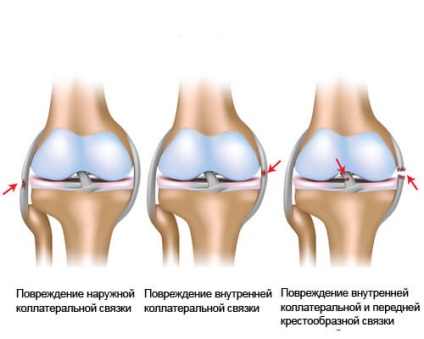

- Tears vagy rándulások, húzódások okozta emelő rakomány alatt hajlítása, sikertelen ugrik. Sérülést az oldalsó ínszalag a közös lehet sérülnek meg, amikor a láb egyenes. Csúszás, akkor kap egy rándulás, ha jelen van a nyomaték.

Segítségével inak térd artikulálja a csontokat. Bármilyen furcsa mozgás vagy stroke vezet sérülés és a térd szalagok. Ez lehet egyszerű, ha nincs arra szükség, hogy a műtét és összetett, amikor egy személy lehet béna anélkül, hogy megfelelő kezelést.